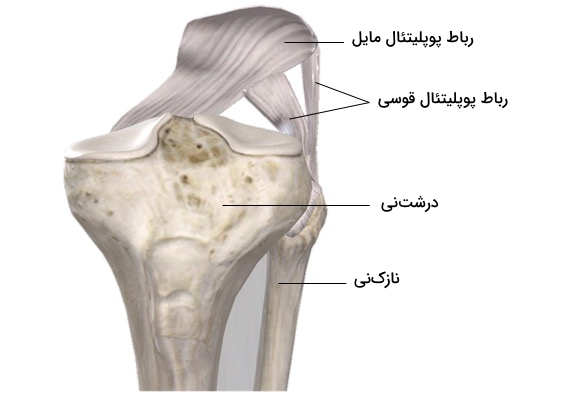

رباط پوپلیتئال مایل

رباط پوپلیتئال مایل که به نام «رباط بورژری» (Bourgery Ligament) نیز شناخته میشود، حاصل گسترش تاندون نیمغشایی است. این رباط از ناحیه پشتی کوندیل داخلی درشتنی منشأ میگیرد و به صورت مایل به سمت بالا و خارج کشیده میشود تا به کوندیل خارجی استخوان فمور متصل شود. این رباط با عبور از حفره بین کوندیلی قادر به تقویت بخش پشتی کپسول مفصل است. در نهایت رباط پوپلیتئال مایل به بخش مرکزی کپسول مفصل می پیوندد.

رباط پوپلیتئال قوسی

رباط پوپلیتئال قوسی نواری ضخیم و فیبری است که از بخش پشتی سر استخوان نازکنی منشأ میگیرد و به صورت قوسی به سمت بالا و داخل حرکت میکند تا به بخش پشتی کپسول مفصل زانو متصل شود. این رباط بخش جانبی پشت کپسول مفصل زانو را تقویت میکند و همراه با رباط پوپلیتئال مایل، از کشیدگی بیش از حد مفصل زانو جلوگیری میکند.